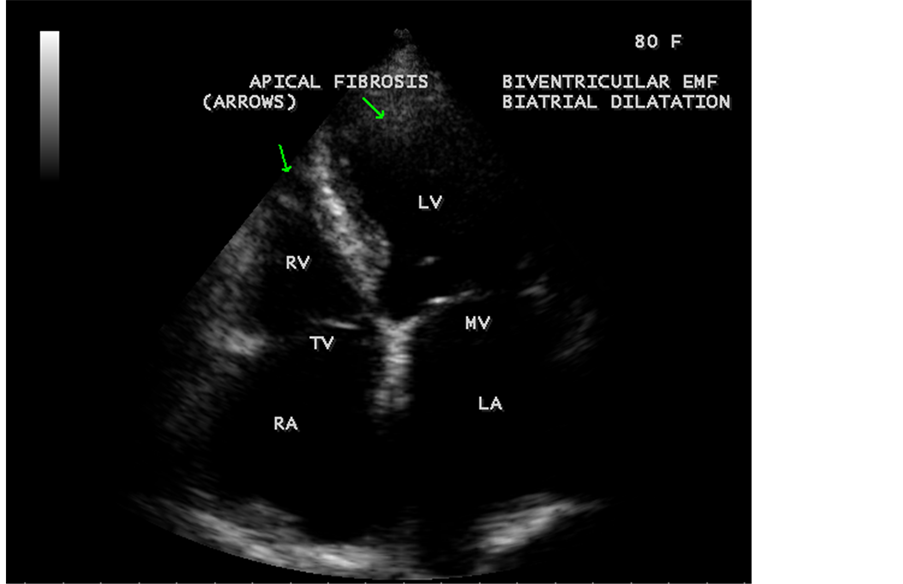

Figure 33. Endomyocardial fibrosis with biatrial enlargement in an 80-year-old female suggesting biventricular EMF ( [18] , Figure 4).